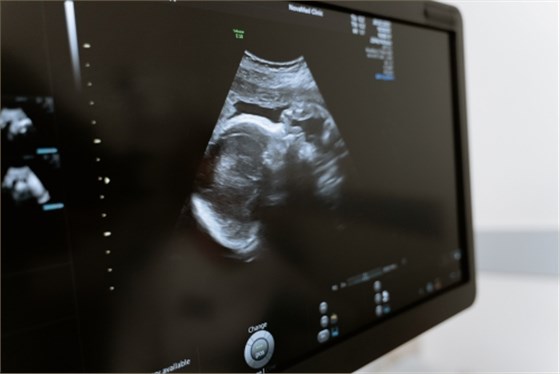

嬰兒髖關(guān)節(jié)超聲檢查,是為了檢查髖關(guān)節(jié)發(fā)育情況、測(cè)量髖關(guān)節(jié)包容間隙、觀察髖關(guān)節(jié)是否有增生、脫位、股骨頭壞死等情況。操作時(shí)一般會(huì)讓患兒取屈膝仰臥位,髖關(guān)節(jié)外展暴露,檢查者戴消毒手套,并進(jìn)行局部消毒,之后讓嬰兒處于仰臥位,雙手搭在膝關(guān)節(jié)上方,用超聲探頭對(duì)髖關(guān)節(jié)進(jìn)行檢查。